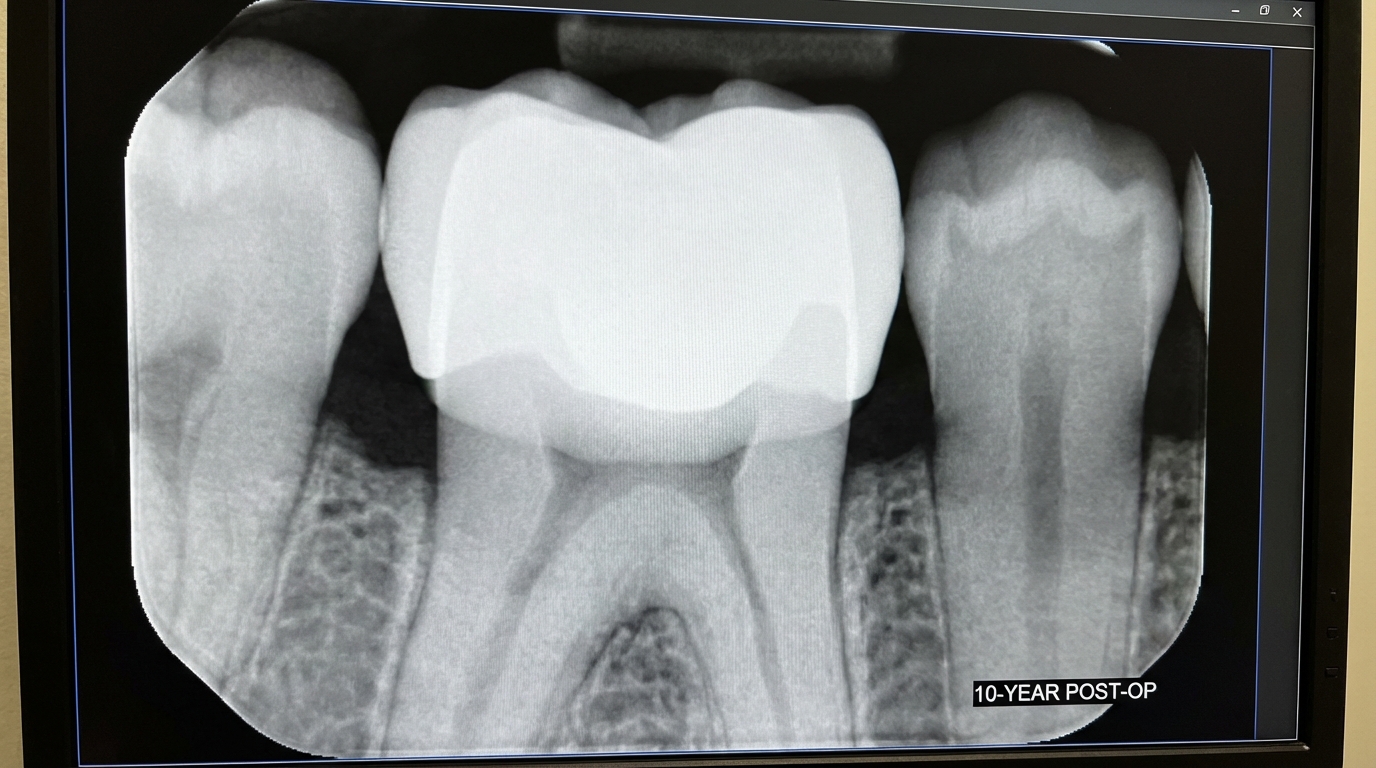

How Long Does a Zirconia Crown Last?

A Zirconia Crown is designed to be a long-term solution, with many lasting 10 to 15 years or even a lifetime with proper care. Its longevity is significantly higher than traditional resin or porcelain-only crowns due to its chemical stability.

What is the typical lifespan?

In a well-maintained mouth, you can expect a zirconia restoration to function perfectly for over a decade. Clinical studies show high success rates even after 10 years of service, provided the crown was seated correctly and the patient maintains good hygiene. The material does not degrade or “age” significantly when exposed to the oral environment.